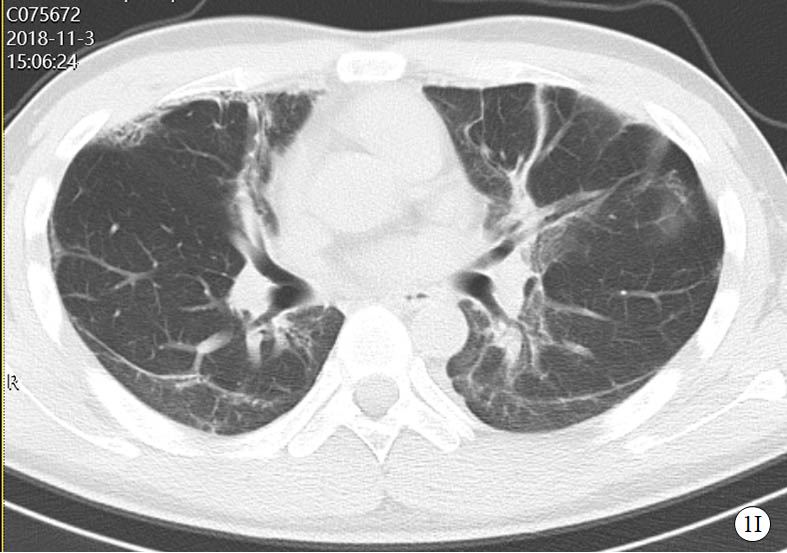

图 1 患者口服百草枯后胸部CT影像学变化

2018-11-03 CT图

2019-01-09 CT图